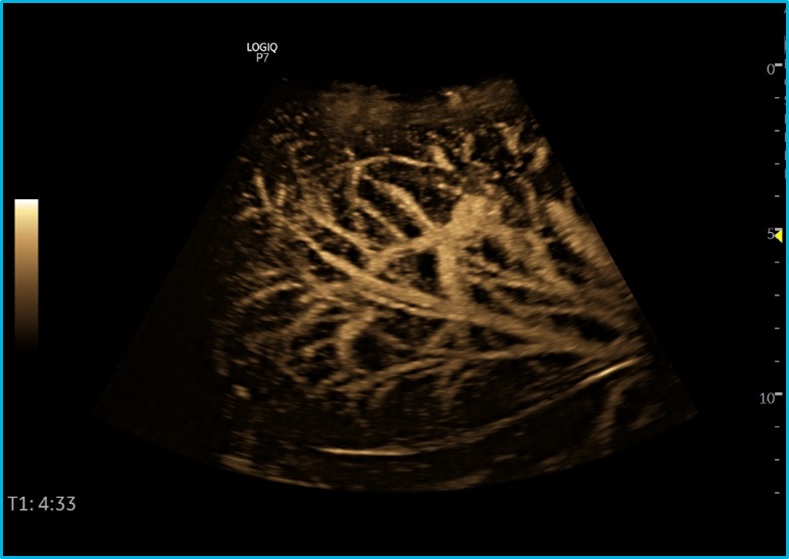

查看完整的图像 Ecograf MultiDickinar多普勒颜色 家具: GE Healthcare. 分类: Ultrasonografie. 水平标签 描述 Ecograf MultiDickinarStaïionar,uşordeulerizat,ConfigurabilDupăeminerinţăulerizatoruluiproiectat pentruaplicaţii产科医生,牙科家,心脏病学,血管放电,尿精,pentrupărţimoi,pediatrice,neonatale,transcranieneşiabi abi abi。 Configuraţia标准Cuprindeşi: Mod B,M,多普勒颜色,多普勒电源,多普勒脉冲 我的页面 - Personalizarea fluxului de lucru 我的教练 - Asistentîn考试 动力助理 - Baterie Pentru Modul备用 预设管理器 - Personalizareaaplicaţiilor 自动优化 - AutoTGC PELÂNGăMultitutudinea de Tehnologii HeluseînConfiguražia标准,echIpmingul渗透i升级-UrioIroare Cu Tehnologii Avansate Predum: Mod Doppler Continuu,TVI / TDI logiq视图 - modul pentruachiziţieimagini panoramice 压力回声 - Ecografie de Stres 心脏菌株 - AFI - MetodăCE SEBazeazăPEMetodă斑点追踪şi护理渗透evidenţiereacontracţieilongitudinalemaximăsistolicăi一个indecelui后嘶嘶声 Elastografie / Elasto Qa - Elastografie CalitativăiCantitativă 流动QA - Analizăcantitatativăpe多普勒颜色 AutoImt - Calcul Semiautomat Al Groosimii Intima-Media B-流 - 模德lucru 2D pentru vizualizarea fluxurilor德三格 - metodăconceputăpentru studiul对ANALIZA stenozelor vasculare,hematoamelor,trombozelor,fistulei AV,activităţiinodulilor,perfuziei renale,morfologieiplăgilorarteriale,turbulenţelorarterei carotide对一个eventualelor sinoase,diferenţieriivaselorCu Fluxuri Mici等 Autoef - Calcularea Automat'aFracţieieejecřie 3D / 4D,Tuişitic,声乐 - Ecografie de Volum hdlive,b-steer CEU - Modul CuSusbtanţă 针指导技术 - Tehnologie Avansation de Ghidare A Acului de Biocksie CE,UN控制APlasăriiAcului Cu ODublăacurateţeAţăReGhidarea套餐Acului 比较助理 - Posibilitatea de比较富有atminilor din考试ăridiferite 扫描助理 - Stabilirea Protocoalelor de Scanare Module DeAnalizë专业:测量辅助OB,测量辅助乳房,乳房生产率şI甲状腺生产率 Traductor de Tip Biplan Cu Ungiul de Viziulizare de Peste 125 de等级 omniview. Imagini Clinice. 查看完整的图像 查看完整的图像 查看完整的图像 查看完整的图像 查看完整的图像 查看完整的图像 查看完整的图像 查看完整的图像 descarcă. descarcō: Broşurălogiq p7. Broşurălogiq p7 gi Broşurălogiq p7 - 肝脏 教育 Platforma logiqclub a fost dezvoltatăpentru a sussilor de sistemee de Ecografie logiqşipentru a puneziia incestora cele Mai NoiInformaţiidespre de实践ă医疗,Articoleşimaialespentruaîncurajaschimbul deExperieţăţăidearăspundeTuturorîntrebăriloruterizatorilor护理Folosesc Ecografele Logiq。 Cuînregistraresimplălogiqclubdepăşeşteştearelede timpşispaţiuşiunşteulerizatoriide Ecografe Logiq Pentru Un Act Medical La CeleMaiînalte标准。 Link-uldeînregistrare:https://www.logiqclub.net/emea/home. 视频 GE Healthcare Logiq P9和Logiq P7超声概述视频 GE Healthcare Logiq P9和Logiq P7超声概述视频的视频 专业: ati. Cardiologie Chirurgie General 内分泌 Gastroenterologie Medicina de Familie Medicina de Uragenta Medicina Interna. nefrologie. Neonatologie. 产科 - Ginecologie Radiologie - Imagisistică医疗¶ 恢复医疗 Reumatologie